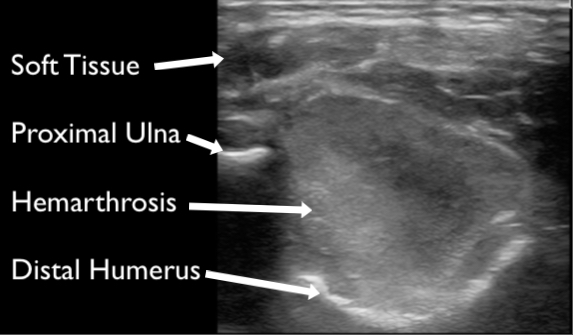

In general, fractures are easier to visualize while scanning along the long axis of the bone. Begin on normal bone and appreciate the bright white/hyperechoic bony cortex and shadowing deep to the cortex. Trace the hyperechoic cortex towards the region of pain and evaluate for disruption of the cortex. A break in the cortex is the fracture (Figures 9). Joint spaces may also demonstrate “breaks” in the cortex, but appear different than fractures with smooth borders and in predictable locations. When a fracture is identified take note of the angulation and displacement. You may freeze the image and measure the distance of displacement with calipers. Continue scanning to evaluate for other associated fractures or fragments. Remove the transducer and image the fracture from another surface to further evaluate for angulation and displacement. For example, if a fracture is identified while scanning a patient anterior radius also evaluate the fracture from the lateral aspect of the arm to appreciate how the fractured fragment is positioned in three dimensions. Lastly, hemarthrosis may be present and should raise the clinical suspicion for fracture even if one is not readily identified (Figure 10).

Figure 10. A large hemarthrosis visualized at the elbow in a grade one supracondylar fracture.